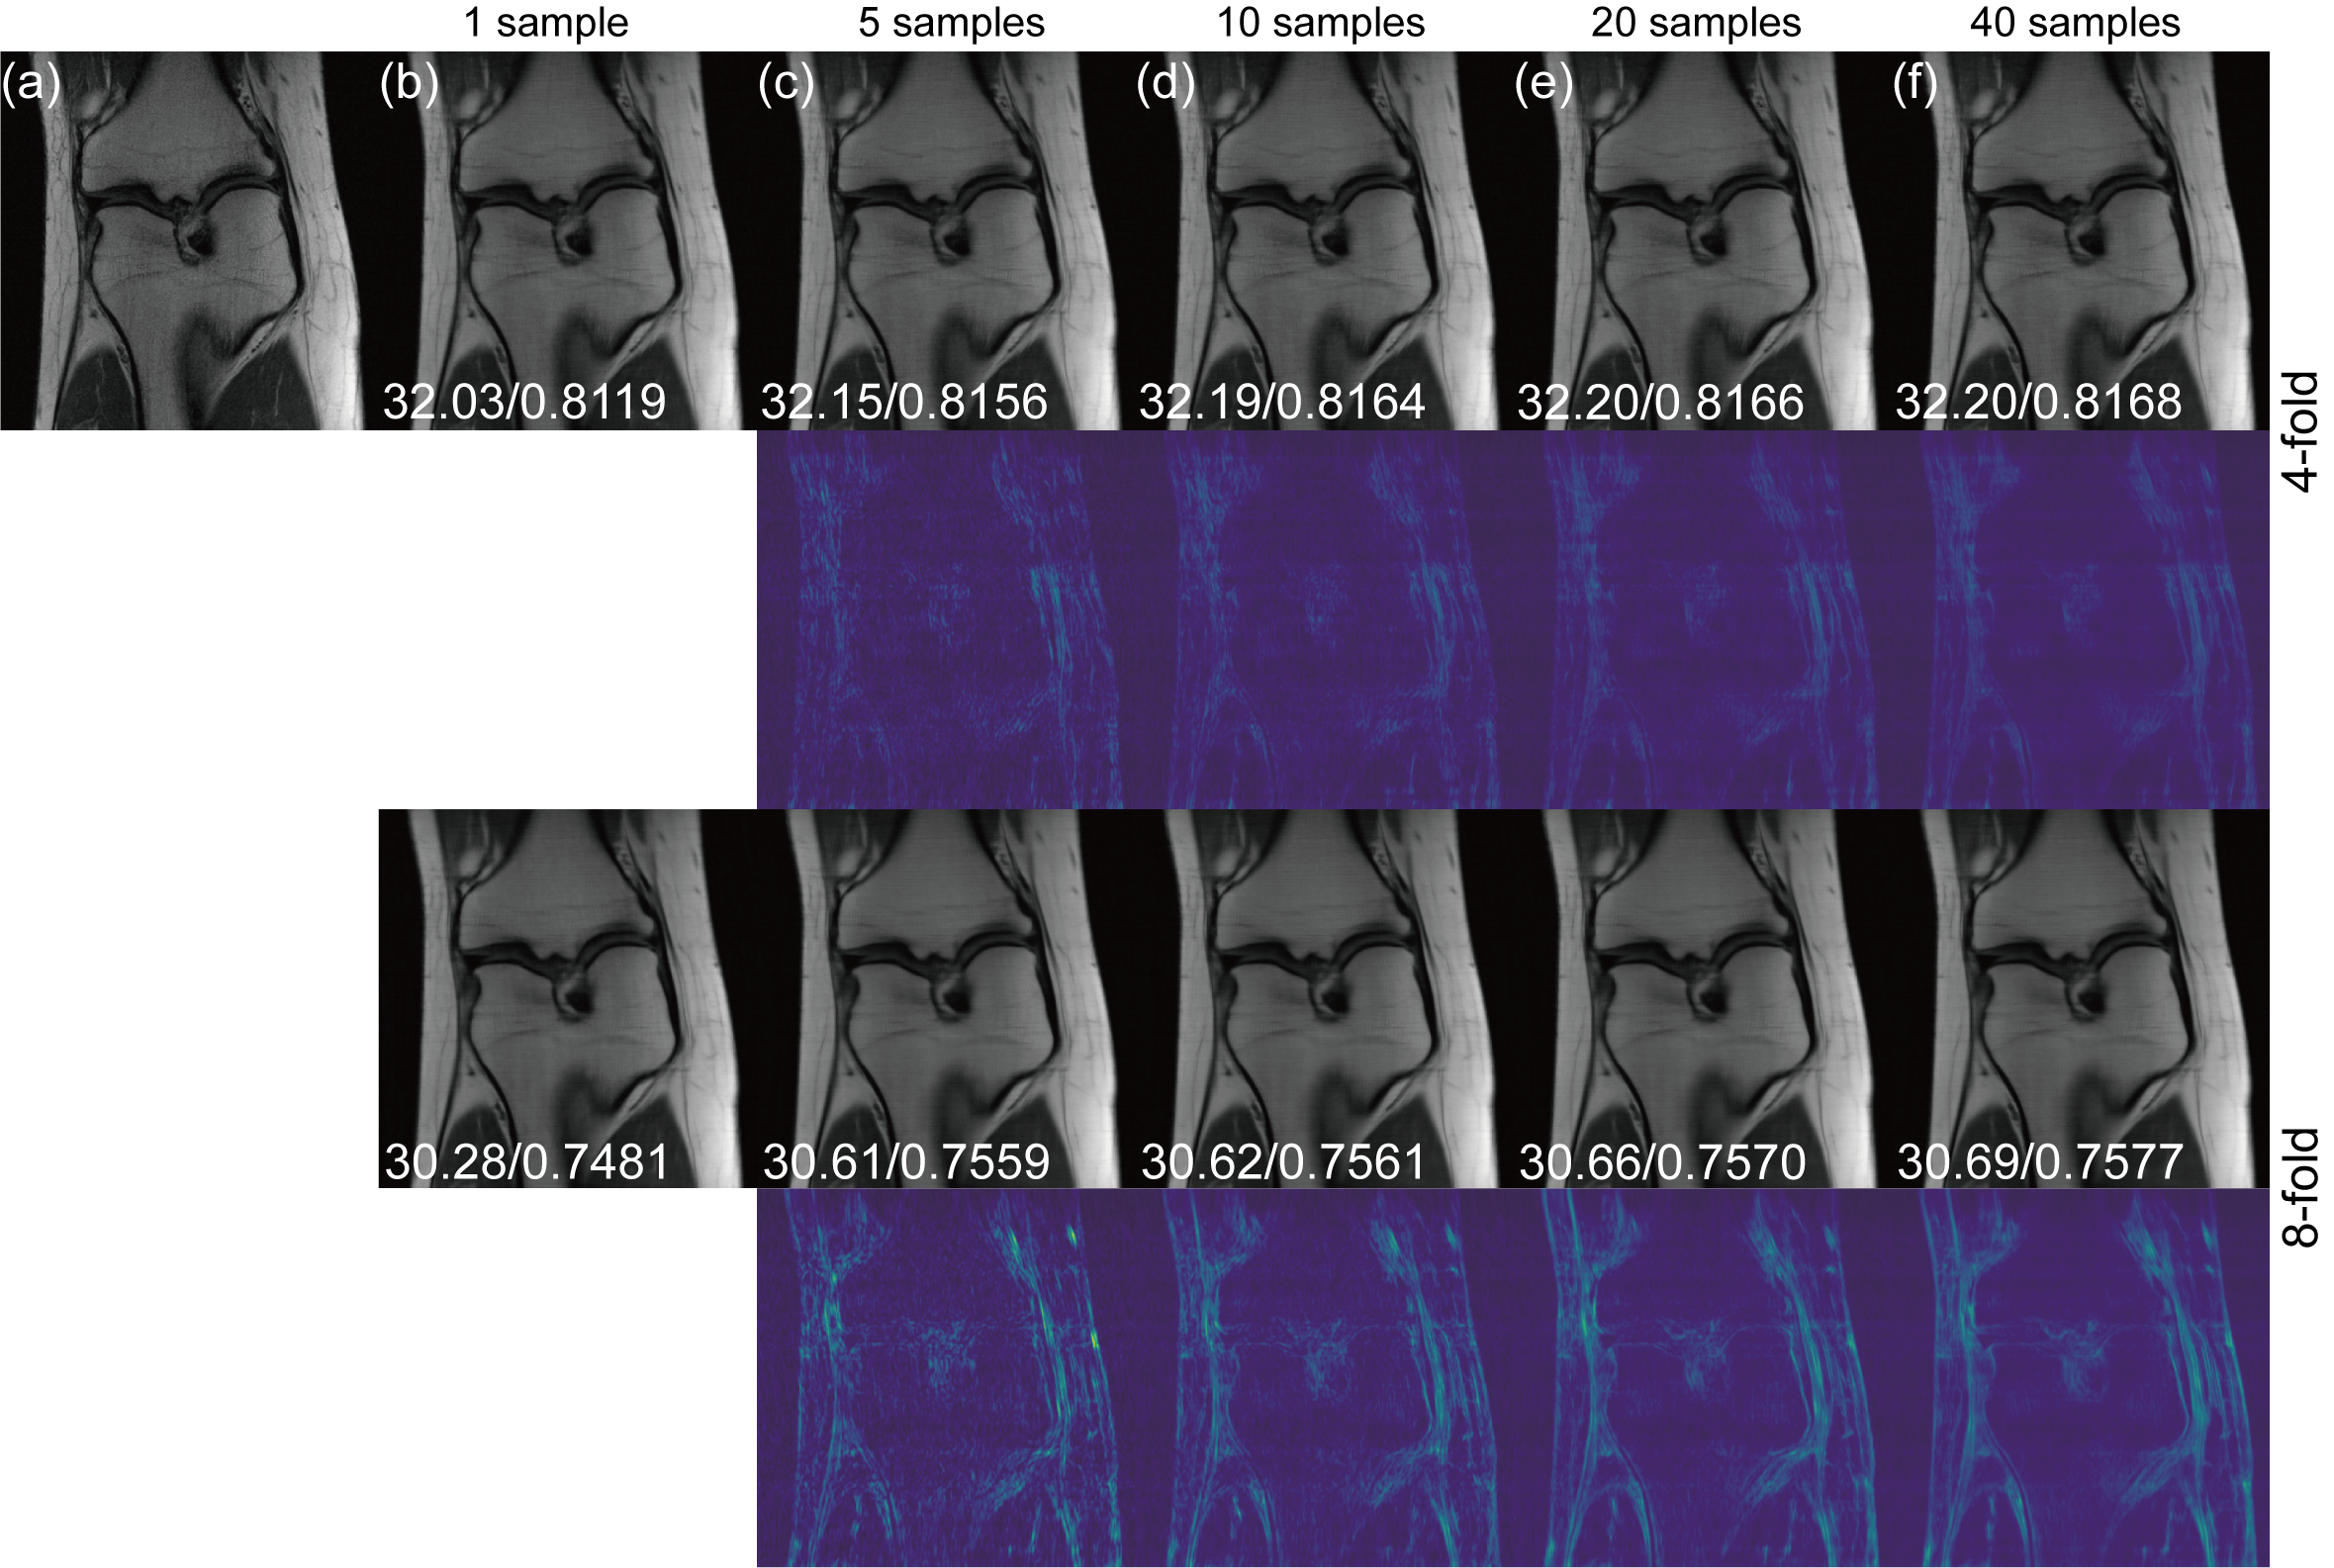

As an image generation model, diffusion-based method can output multiple reconstructions given a starting point. The original noise-based diffusion models can generate multiple images from noises. Later conditional diffusion models are capable of performing multiple samplings given the same starting point. Here we also explore the effects of multiple samplings of our model. Examples are shown in Fig. 5. For multiple sampling settings, we take the average in pixel level from all sampling images as the final output image. The uncertainty map is calculated by taking the standard deviation among all samples in pixel level. As the acceleration factor increases, the corresponding uncertainty increases as well. Corresponding PSNR/SSIM are labelled together with the image. We found that when the sampling number is 5-10, the improvements in metrics are rather noticeable. As the sampling number increases, the enhancement converges. Note that more samplings lead to a longer reconstruction time and the averaging over multiple samplings can lead to a smoothness for the final reconstruction, which may hamper the image details. Taking these into consideration, we simply take single sampling for our reconstruction.